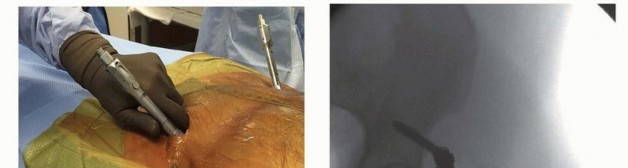

Subcutaneous Anterior Internal Pelvic Fixation

Internalization of anterior pelvic fixation may be preferable when external fixation is planned as the definitive treatment modality. This is especially true in obese patients where a traditional external fixator may be necessarily placed farther from bony anatomy, affording less stability and predisposing pin tracts to infection. Internalized, subcutaneous fixators show lower rates of infection and loosening, but heterotopic ossification is a concern and lateral femoral cutaneous nerve irritation is somewhat common. 30 The technique depicted in this text employs cannulated instruments and implants commonly employed for posterior spinal fixation. Several similar procedures have evolved using similar techniques with plates, screws, pins, or alternative devices. The patient is positioned supine on radiolucent table, and ability to obtain the necessary C-arm positioning for the appropriate fluoroscopic views is confirmed prior to draping.

The skin is prepared and draped from umbilicus to the upper thigh.

If needed for reduction, the lower extremities may be included; for example, if performing iliosacral screw placement concurrently, many surgeons prefer to perform posterior stabilization prior to anterior. The anterior superior iliac spine is used as a superficial landmark; the incision and starting point is approximately 2 cm caudal and 1 cm medial to this point. Placement of the incision over the AIIS is confirmed with fluoroscopy. Incision is made obliquely in line with skin folds over the AIIS, and dissection is carried down between sartorius and tensor fascia lata down to AIIS. A Jamshidi needle is pressed between the cortices of the ilium, directed toward the posterior superior iliac spine, as visualized on the obturator oblique outlet fluoroscopic view (as noted in the Supraacetabular

Technique section of this chapter) ( TECH FIG 7 A,B).

The obturator inlet view is used for surveillance of the needle as well as the subsequent guidewire and screw advancement between the tables of the ilium, as noted previously. The guidewire of the pedicle screw system is then positioned and advanced through the needle, between the tables of the ilium toward the posterior superior iliac spine under fluoroscopic control, and length is measured.

TECH FIG 7 • A. Jamshidi needle with guidewire in place in supraacetabular bone. B. Fluoroscopy obturator outlet view showing placement of guidewire via Jamshidi needle.

It is essential when selecting screw length to consider that the screw should stand proud about 1. 5 to 4 cm from bone to allow the connecting rod to lie subcutaneously without compression of traversing neurovascular structures (iliac vessels, femoral nerve). Patient habitus should be considered when contemplating this additional length, as the fixator can be customized to match patient body habitus, with longer lengths for obese patients and shorter lengths for thin patients to avoid hardware prominence. 29 A tap can be employed if desired, especially if a plain screw is being used as in part of a noncannulated system ( TECH FIG 7 C-E). A single 7.0- to 8.5-mm cannulated uniaxial or polyaxial pedicle screw is placed over the guidewire using the screw assembly ( TECH FIG 7 F,G). The procedure is repeated on the contralateral side either simultaneously or sequentially after placement of the first screw ( TECH FIG 7H). The 5.5- to 6.5-mm titanium connecting rod is precontoured with an anterior bow to comply with individual patient habitus and pelvic morphology. This rod is inserted above the abdominal fascia via a subcutaneous tunnel using the rod holder assembly to meet the contralateral screw ( TECH FIG 7 I,J). The “bikini line” has been described to guide rod placement subcutaneously and exists as a skin fold essentially connecting the two AIIS. This line exists, on average, 5-7 cm above the pubic symphysis. 31 The individual contouring of the rod is a variable that must be considered when taking care to avoid compression of vital structures, as external iliac vessels are, on average, a mere 2.2 cm posterior to the rod when done correctly. 16 Once the rod is captured and locked by an end cap on one side, rotational reduction can be finalized, closing the pelvis anteriorly. Use of a system-specific compression tool is feasible at this point prior to applying the second end cap, locking the fixator. Supra-acetabular compression has been observed to

infer some modest degree of posterior reduction as well. 8

A rod cutter is employed to eliminate excessive lateral overhang of the rod if desired. Incisions are irrigated and closed according to surgeon preference, with the screw heads left above fascia ( TECH FIG 7K). The surgeon should bear in mind that internalization of the fixator in the manner described mandates a return to the operating room for removal after healing of fractures (typically between 3 to 6 months). 322